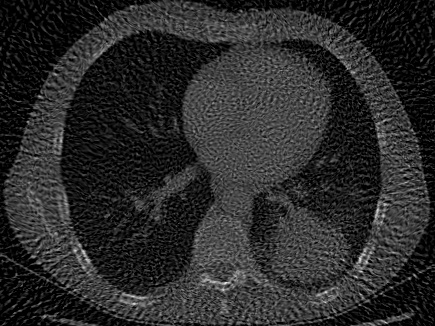

| Computed Tomography (CT) [28] | 2D | X-ray CT scan of a human chest, used to evaluate signal recovery in a classic underdetermined inverse problem. |

For CT experiments, we train models on a real chest CT slice from the dataset in Clark et al. [28], which was also used in WIRE [16]. The training data was 100 projection measurements of the original 326435 chest CT slice, forming a 100435 sinogram equivalent to approximately 30% of the total pixel count in the original image. Since this inverse problem is inherently underdetermined, we apply TV regularization in our Grid model. The TV hyperparameter was tuned using the classic Shepp-Logan phantom image [37] as a reconstruction target.